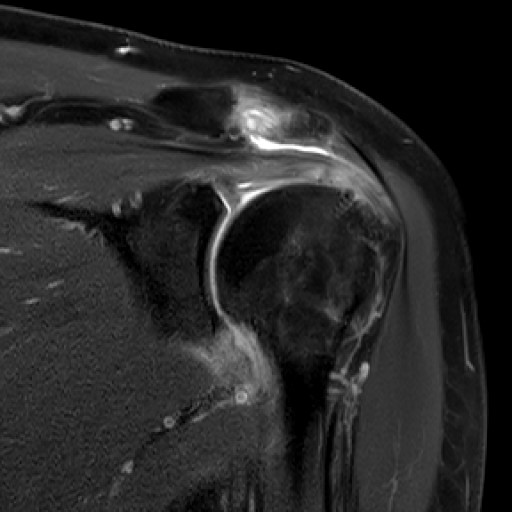

Zum wiederholten Mal war Dr. Georg Öttl als Vorsitzender in der Schultersession/obere Extremität eingeladen worden, in der Sportverletzungen und Überlastungen der Schulter diskutiert wurden.

Die Fachveranstaltung richtete sich an Radiologen in Klinik und Praxis mit einem besonderen Interesse an muskuloskelettaler Radiologie sowie speziell der Diagnostik von Sportverletzungen. Sie war aber auch für Orthopäden und Rehabilitationsspezialisten geeignet, die sich über aktuelle Möglichkeiten der bildgebenden Diagnostik bei Sportverletzungen und deren Einfluss auf die Therapieentscheidungen informieren wollten.